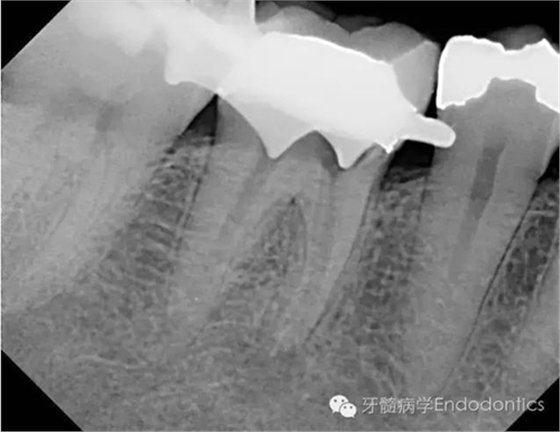

圖4.取出根管內(nèi)充填物后拍攝的X線片